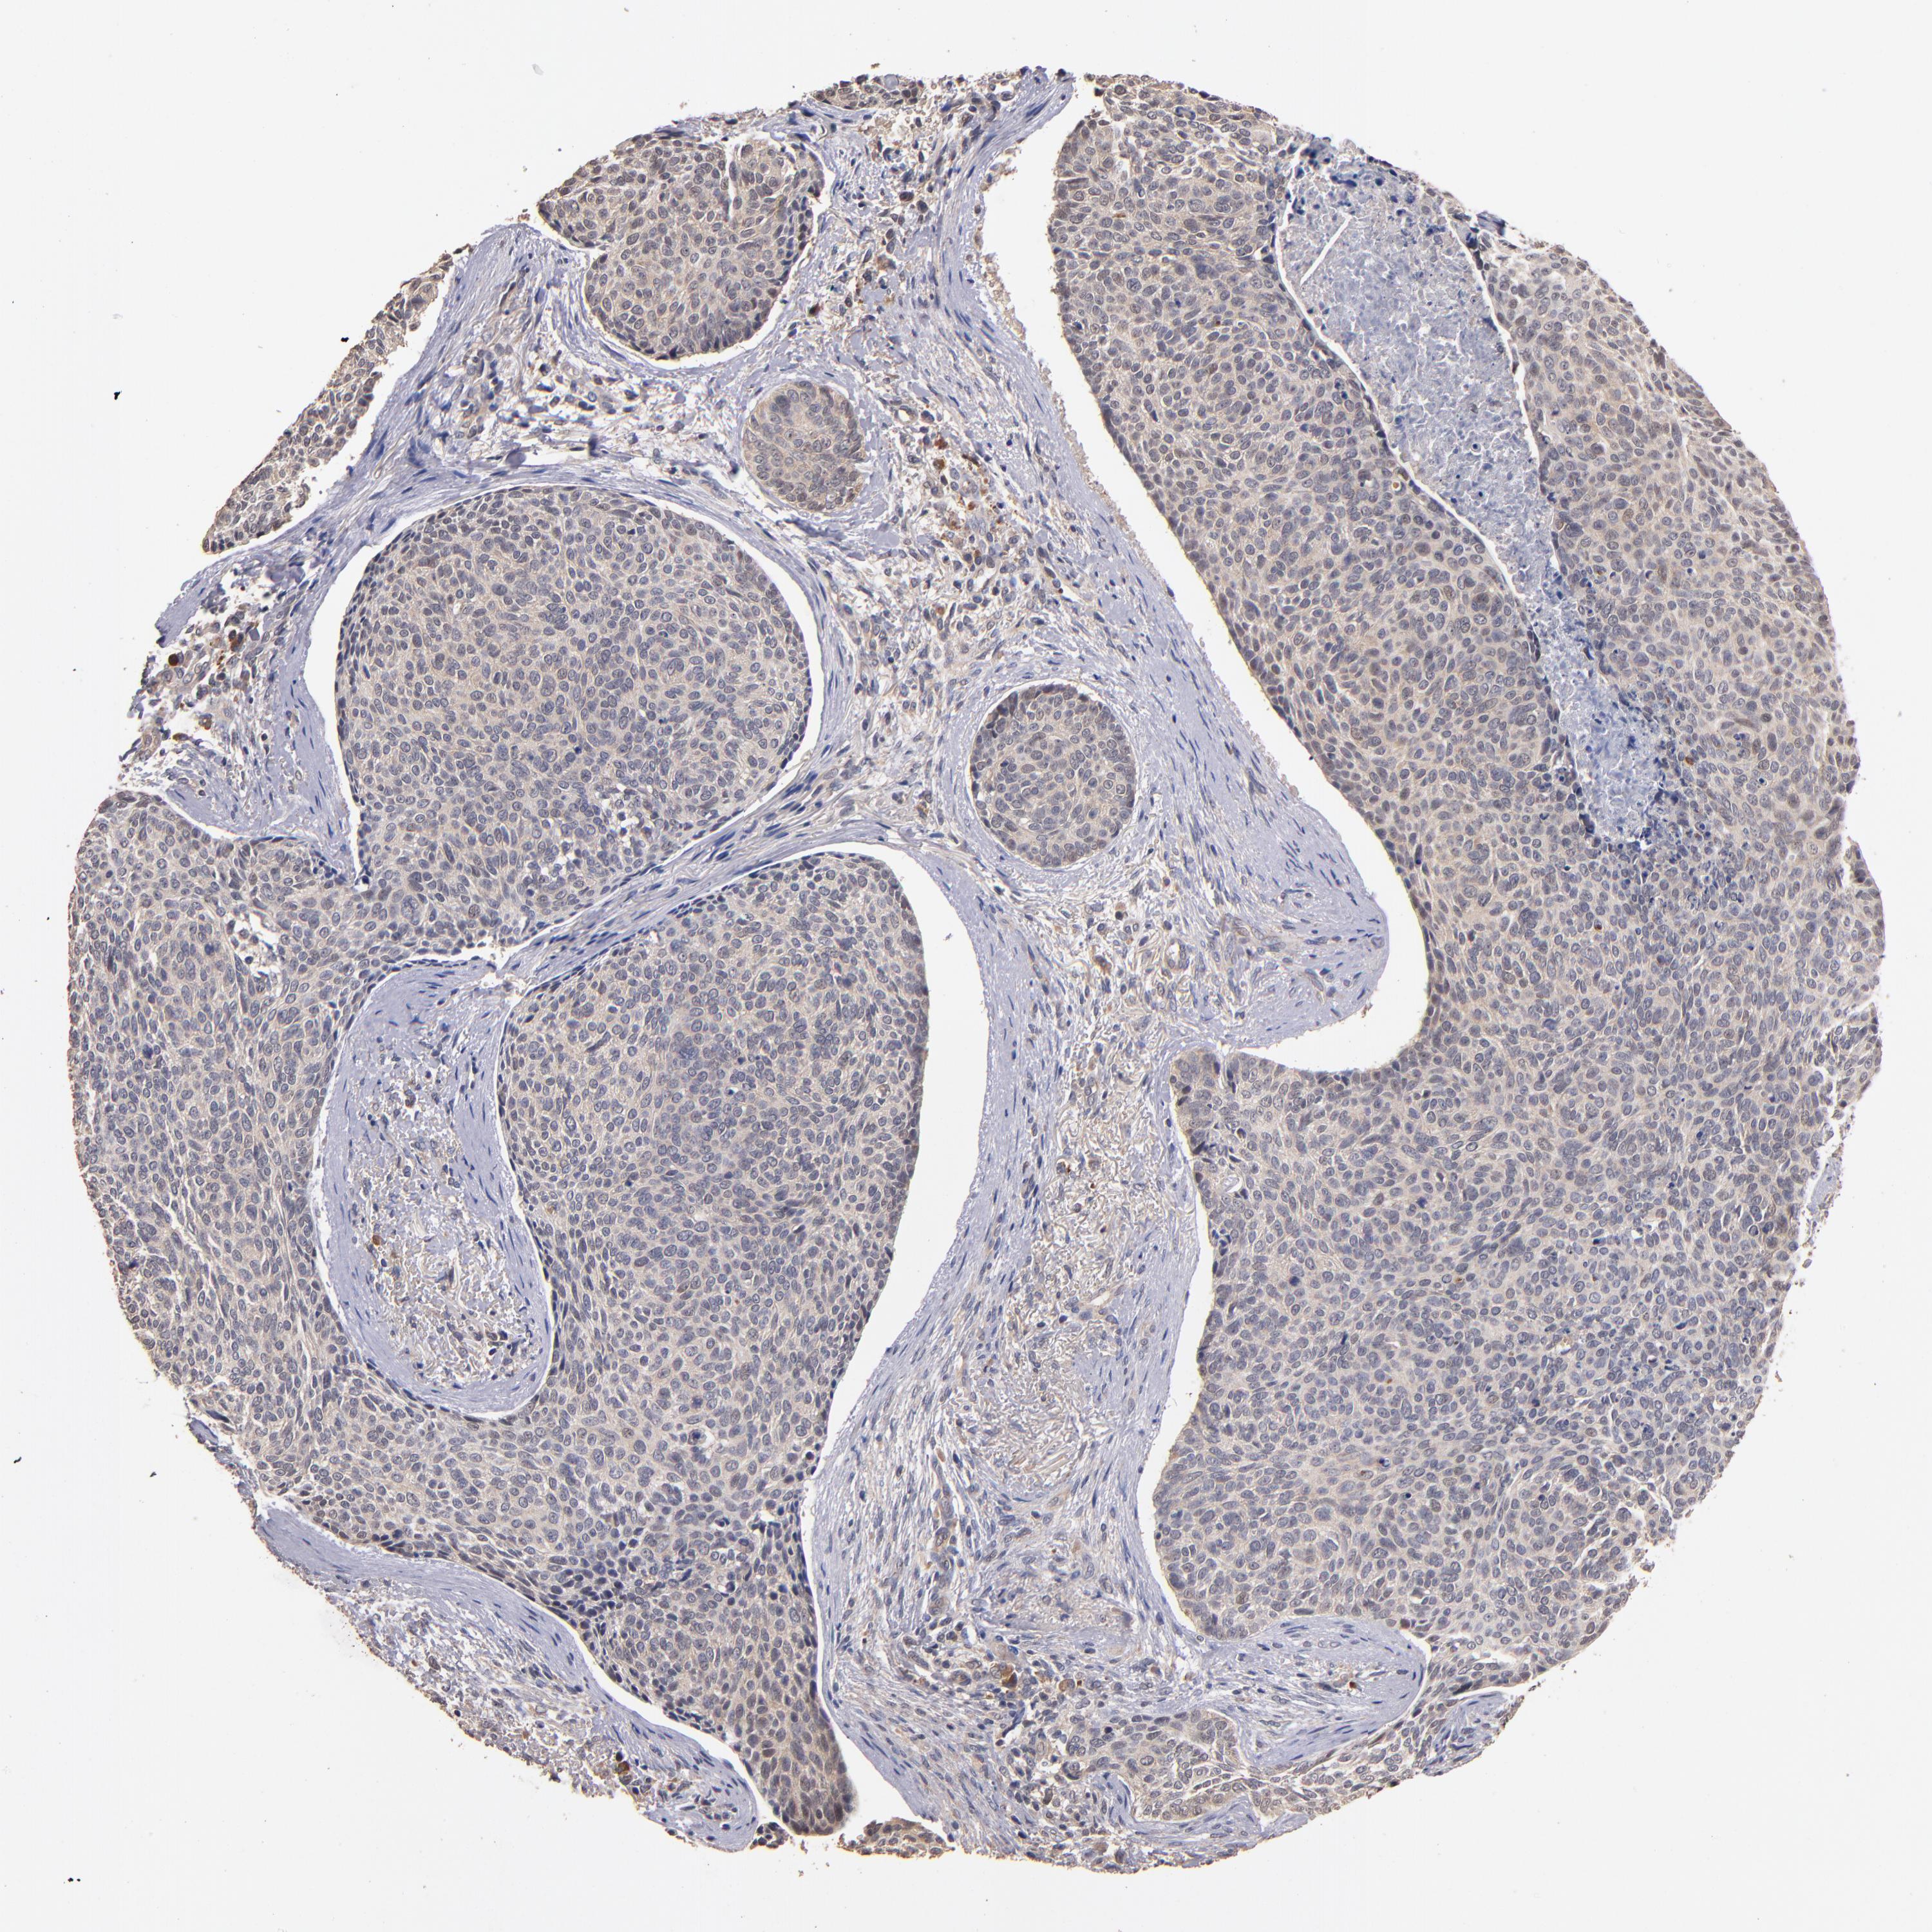

Basal cell and squamous cell cancer

SKIN CANCER - Protein expressioni

A mouse-over function shows sample information and annotation data. Click on an image to view it in a full screen mode. Samples can be filtered based on level of antibody staining by selecting one or several of the following categories: high, medium, low and not detected. The assay and annotation is described here.

Antibody stainingi

Antibody staining in the annotated cell types in the current human tissue is reported as not detected, low, medium, or high, based on conventional immunohistochemistry profiling in selected tissues. This score is based on the combination of the staining intensity and fraction of stained cells.

Each image is clickable and will lead to virtual microscopy that enables deeper exploration of all samples and also displays staining intensity scores, fraction scores and subcellular localization as well as patient and tissue information for each sample.

Antibody CAB046029

Basal cell carcinoma